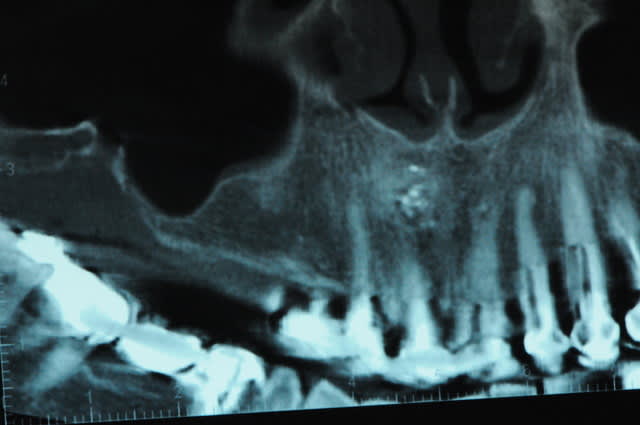

scanner...

aspect des crêtes et début du sinus lift.

l'os était tellement fin qu'il n'y avait presque pas besoin de la piezo.